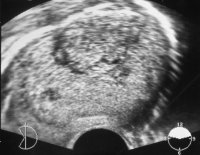

Bei einer entsprechenden Untersuchung nach 5 Jahren fiel ein tumorverdächtiger Knoten im linken Resthoden auf. Bei dem Ersttumor auf der rechten Seite war eine Probebiopsie auch aus dem linken Hoden entnommen worden, die tumorfrei war.

Sonographisch ergab sich ein umschriebener, ca. 2 cm großer, inhomoger tumorverdächtiger Bezirk im linken Hoden (Abbildung 11).

Die tumormarker waren erhöht: AFP 1920 ng/ml, hCG 80,2 mIU/ml (Abbildung 12).